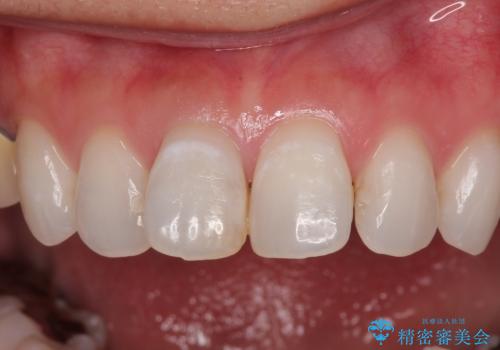

- 前歯の変色と、以前装着したクラウンが黄ばんできたことを気にして来院された患者様です。

前歯に変色が起こる場合、神経組織の失活により引き起こる可能性が高いため、診察を行ったところ、根尖部の病変や叩いたときの痛みなどが認められました。

まずは根管治療を行い、痛みの消退を確認してからオールセラミッククラウンによる補綴治療を行うこととしました。

色がやや白いと感じましたが、ご自身でホームホワイトニングをされているそうで、今後周辺の歯を白くしていくとのことでした。